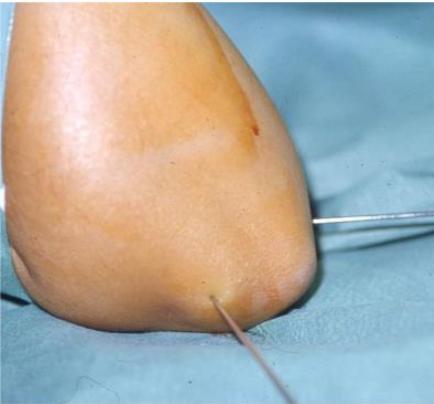

Displaced fractures:

- Closed reduction and fixation with K-wires & slab

Case Example: 6-year-old girl, fell from swing

Initial injury

After reduction

3 months follow-up

2 years follow-up